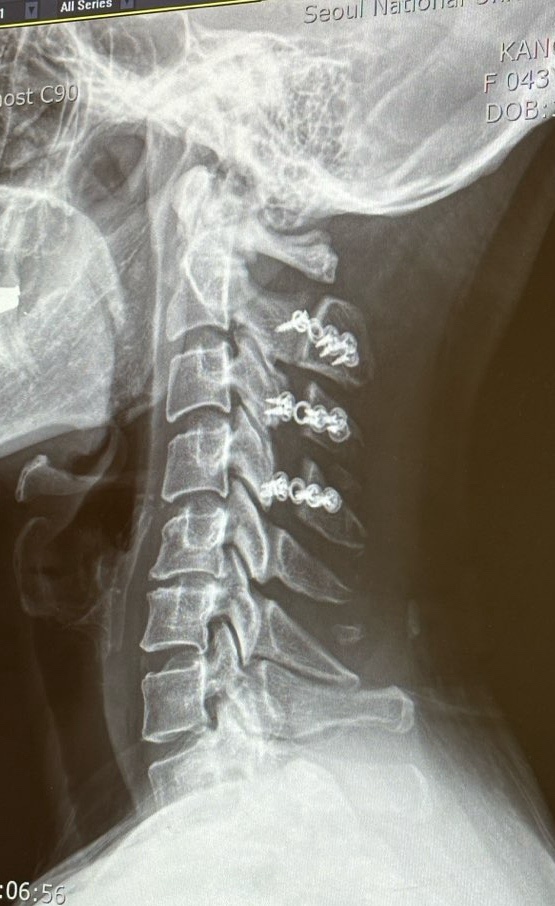

서울대학교병원 암센터 진료/ 척수종양 수술 1년후 진료 /천안순천향대학교병원 방사선종양학과 진료 /12/2024년12월

’기록‘의 의미가 제일 크고, 척수종양발견으로 혼란스러울 환자분들을 위한 의미가 두번째로 큽니다. 글...

서울대학교병원 암센터 진료/ 척수종양 수술 7개월 후/11/ 2024년6월

지난 6월 ㅅㅇㄷㅎㄱ병원 진료를 보러 다녀왔다. (수술 7개월 후) 약이 없어도 너무 힘들지만 약의 도움을 ...